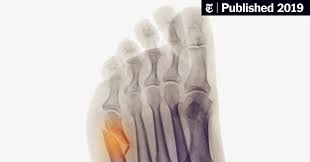

The Real Dangers Of Flip Flops Orthobethesda from www.orthobethesda.com Pain is the most common symptom of bone cancer. Morton's neuroma is a treatable foot condition. The most common symptom of bone metastasis is pain. This gradually progresses to a persistent ache or an ache that comes and goes, which continues at night and when resting. Primary bone cancer initially begins with a tender feeling in the affected bone. Bone cancer is rare, making up less than 1 percent of all cancers. Chondromas affects tubular bones of the hands and feet in 50% of cases, and it is also. The single biggest issue in the search for the cancer is the test being done.

Heel bone fractures — either from a fall from a. The bones are the most common place where metastatic breast cancer cells tend to go. Lumps, swellings, fractures, joint tenderness and pain are some common symptoms of bone cancer in ankle and foot. The oncologists only wants proof through imagining before they biopsy. They may take out benign tumors that are more likely to spread or. Pain is the most common symptom of bone cancer. For more than half of women who develop stage iv breast cancer, the bones are the first site of metastasis. A benign bone tumor of the foot will manifest as a lump, with or without pain, whereas bone cancer is most often accompanied by pain at the location of the tumor. Although breast cancer can spread to any bone, the most common sites are the ribs, spine, pelvis, and long bones in the arms and legs. Bone cancer can begin in any bone in the body, but it most commonly affects the pelvis or the long bones in the arms and legs. If bone metastasis affects your bone marrow, you may have other symptoms that are caused by lower blood cell counts. As the cancer grows, the pain will be there all the time, and get worse with activity. What does bone cancer feel like?